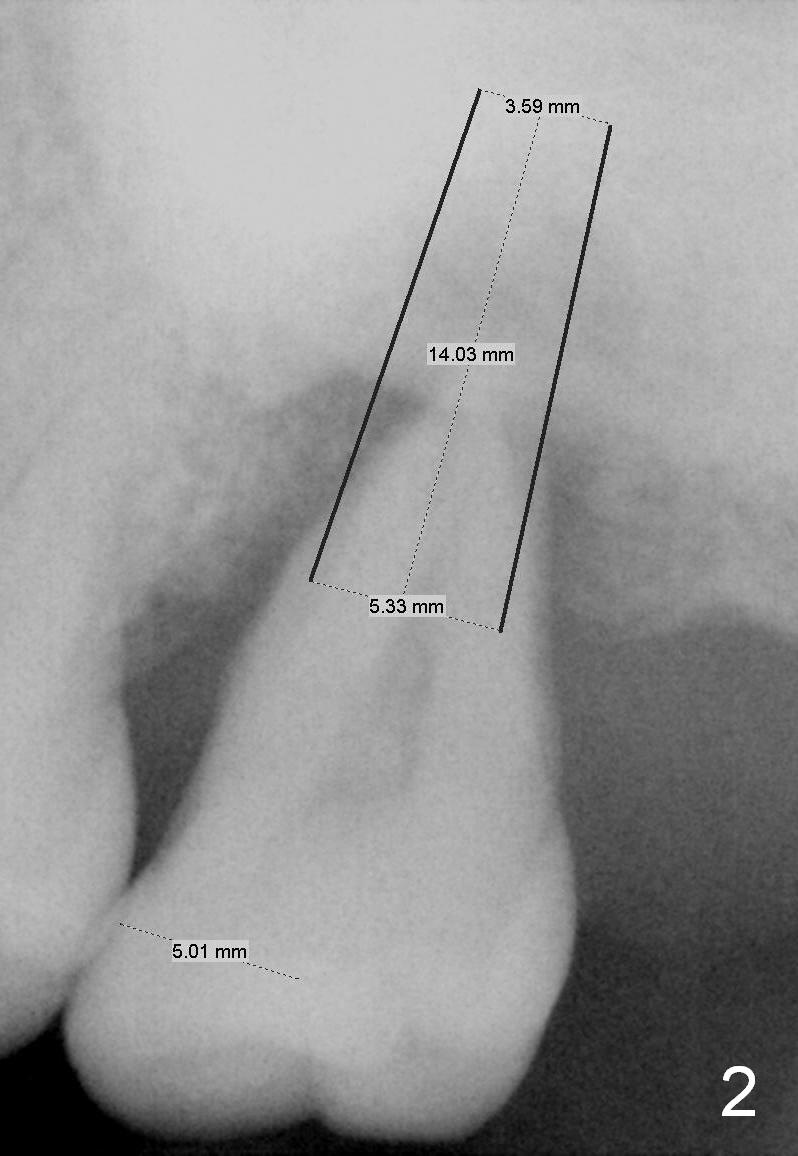

A 49-year-old lady has history of periodontal disease (Fig.1). The teeth #2 and 19 have been extracted and replaced by immediate implants. When she returns, crown is going to be cemented at #19 and delayed implant will be placed at #15. The tooth was extracted 4.5 years ago. No PA has been taken since extraction. Fig.2,3 show design for immediate implant if the tooth were not extracted (*: mesial crest; O: bone graft). Note the orientation of the implant and the space from the neighboring tooth.

#15 blade will be used for access and periosteal elevator for opening osteotomy site. Set implant spacer at 4 mm. Since the maxillary posterior region usually has poor bone density, bone expander kit will be most likely used until 2-3 sizes smaller than the expected implant. The latter will be decided by preop and intraop X-ray.